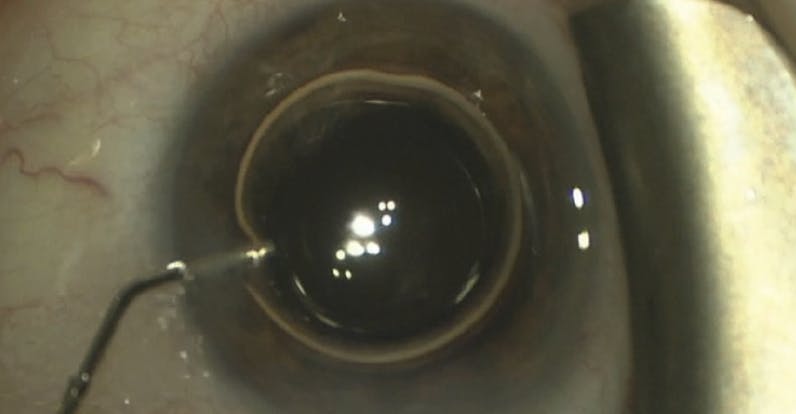

A patient was referred for an elevated IOP of 23 mm Hg despite being on three classes of medication after cataract surgery with iStent (Glaukos) implantation performed 4 months prior. The referring surgeon suspected that the patient’s IOP was unresponsive to the device, as it had seemingly provided no IOP-lowering effect.

Upon examination, the iStents were found to be located in the ciliary body. I performed a 180° gonioscopy-assisted transluminal trabeculotomy in the right tissue plane. IOP decreased to the middle teens mm Hg postoperatively, confirming that the patient’s outflow pathway was functional and the problem was incorrect device placement (Figure).

Proper knowledge of anatomic landmarks is critical for MIGS success.